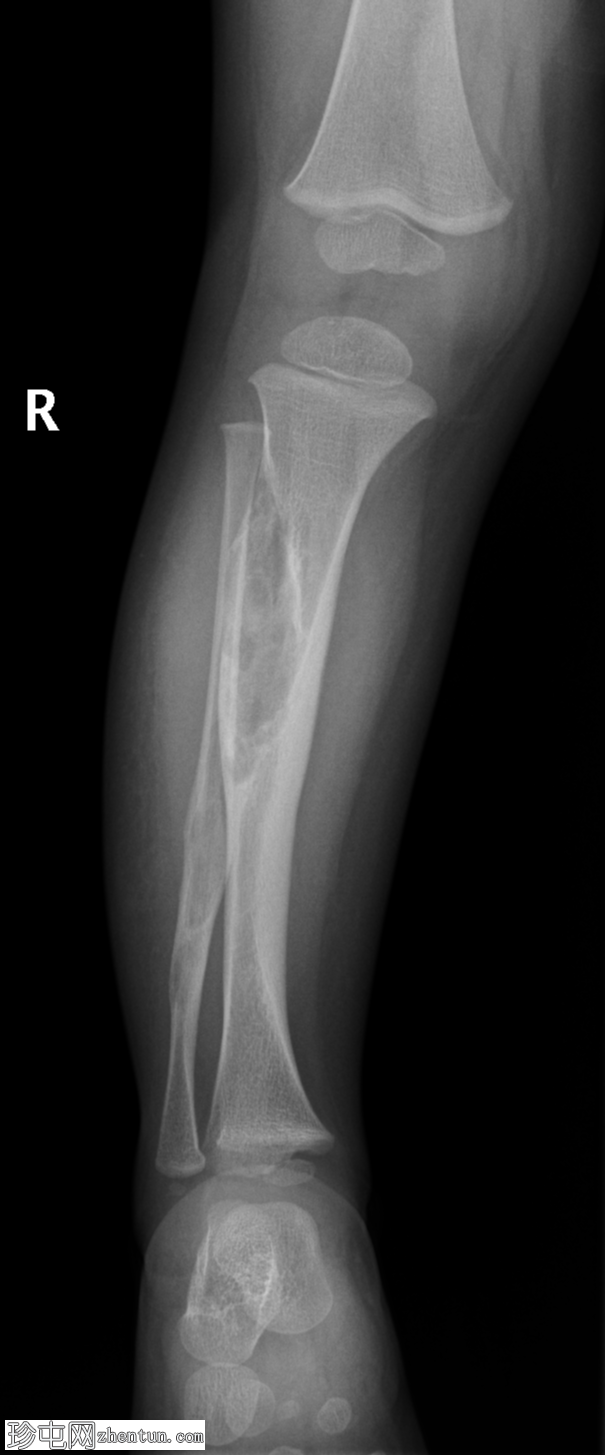

2.jpg

侧位片

右胫骨近端骨干皮质透亮膨胀性病变,边缘硬化较薄(过渡区狭窄),导致前弓形畸形。腓骨远端骨干可见类似病变。未见骨膜反应或病理性骨折。